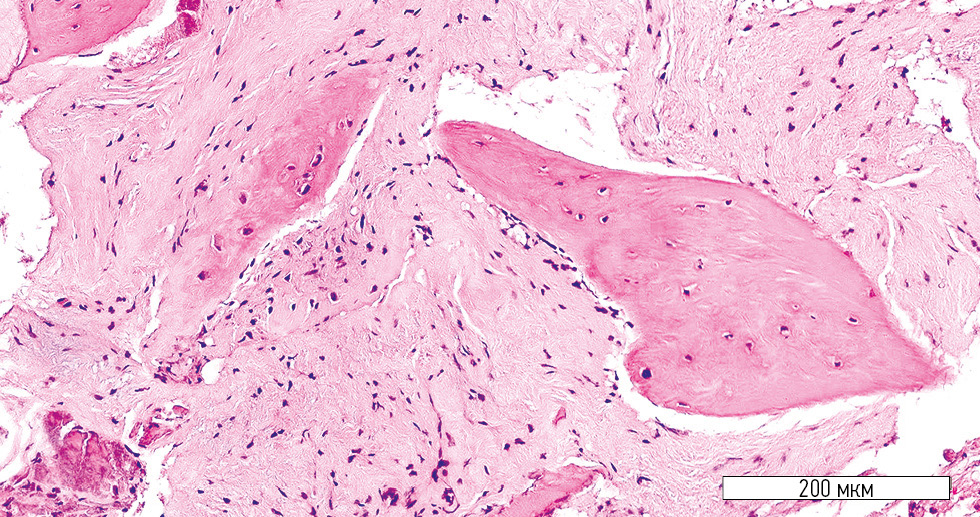

Microscopic evaluation after 4 months revealed substantial differences in the histological architecture of the regenerated bone between the treatment and control groups. In the treatment group, a well-developed stromal component and newly formed bone trabeculae were observed (Fig. 1). The stromal component consisted of densely packed mesenchymal cells with a minimal number of blood vessels per mm2 (Fig. 2). Areas of osteogenesis contained active osteoblasts, and the newly formed bone lamellae showed multiple lacunae, some with osteocytes and isolated osteoblasts (Fig. 3).

Fig. 1. Well-developed stromal component (treatment group). Hematoxylin-eosin stain; original magnification ×100.